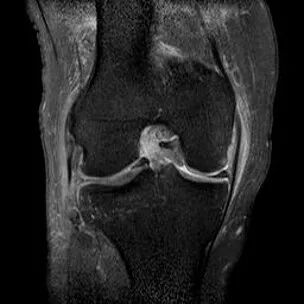

最常见类型:斜行撕裂表现为:在矢状面上见III级高信号到达半月板关节面的上缘或下缘

半月板斜行撕裂